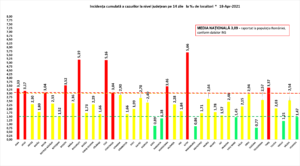

Coeficientul infectărilor cumulate la 14 zile, raportate la 1.000 de locuitori este calculat de către Direcțiile de Sănătate Publică, la nivelul Municipiului București și al județelor. Mai jos aveți graficul realizat în baza raportărilor primite de CNCCI de la Direcțiile de Sănătate Publică: